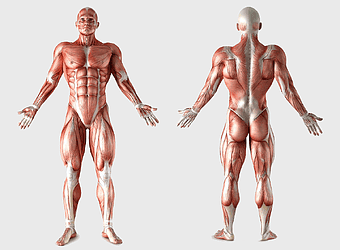

muscular system illustration, human anatomy diagram, fitness professional figure, skeletal muscle structure, muscular development, human body musculature, anatomical study -

human muscular system illustration, muscle anatomy human body, fitness professional bodybuilder, human back and abdomen muscles, anatomical muscle structure, human skeletal muscle system, detailed human muscle chart -

human anatomy illustration, male body diagram, human limb structure, surface anatomy chart, human skeletal outline, full-body medical sketch, human joint depiction -